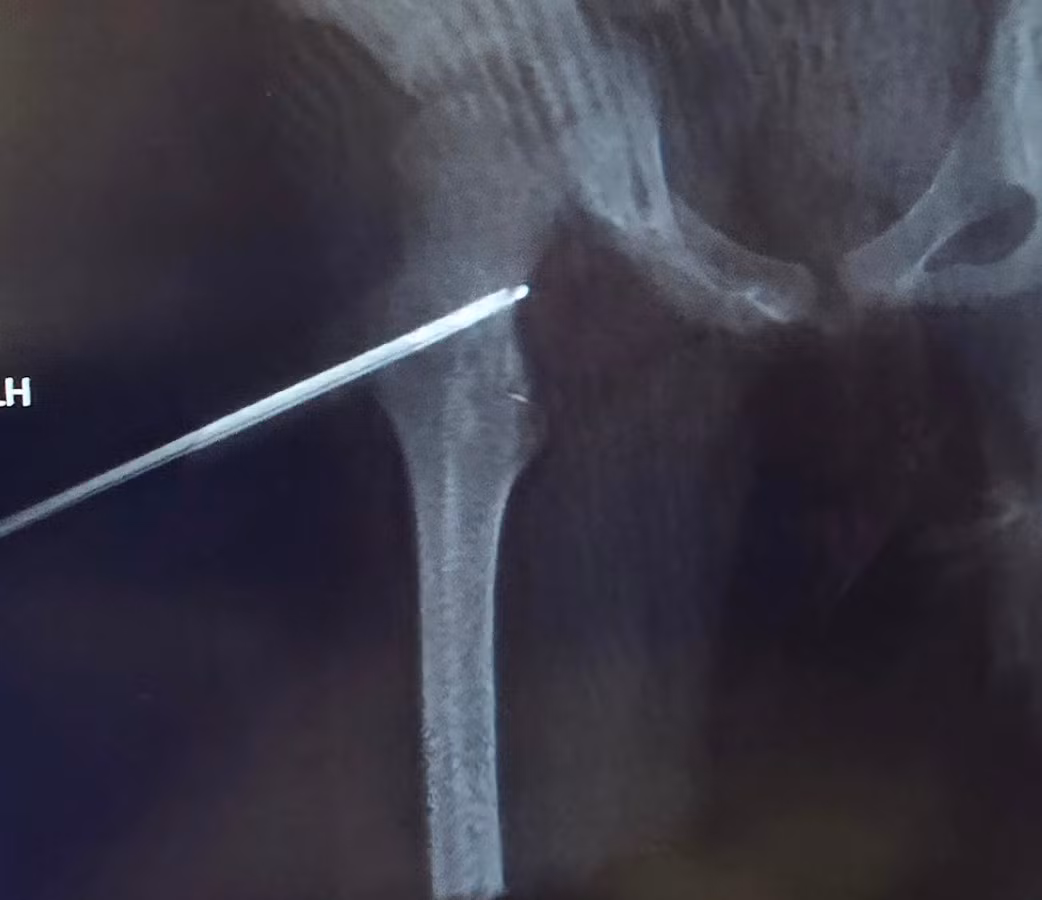

U xương ở vị trí hiếm gặp - Ảnh BSCC

Sau khi thăm khám tại nhiều bệnh viện tuyến tỉnh và trung ương, các bác sĩ xác định nguyên nhân là do một u xương lành tính (osteoid osteoma). Kích thước khối u chỉ 5mm nhưng nằm sâu ở mặt sau và trong của cổ xương đùi , nằm trong bao khớp và sát với bề mặt của khớp háng – vị trí rất khó tiếp cận.

Khối u nằm ở một vị trí cực kỳ khó: mặt sau và trong của cổ xương đùi bên phải, hoàn toàn trong bao khớp. Phẫu thuật gần như không thể vì nếu mổ mở để lấy u, cháu bé có nguy cơ cao bị tổn thương mạch máu nuôi xương, dẫn tới hoại tử chỏm xương đùi, thậm chí phải thay khớp háng khi còn rất nhỏ tuổi.

Can thiệp tiến hành bằng mê nội khí quản, khoan xương qua cổ xương đùi để vào đến khối u xương dưới định vị bằng Siêu âm, Fluoscopy và Conbeam CT. Đốt sóng cao tần bằng kim có đầu đốt dài 0,7 cm.